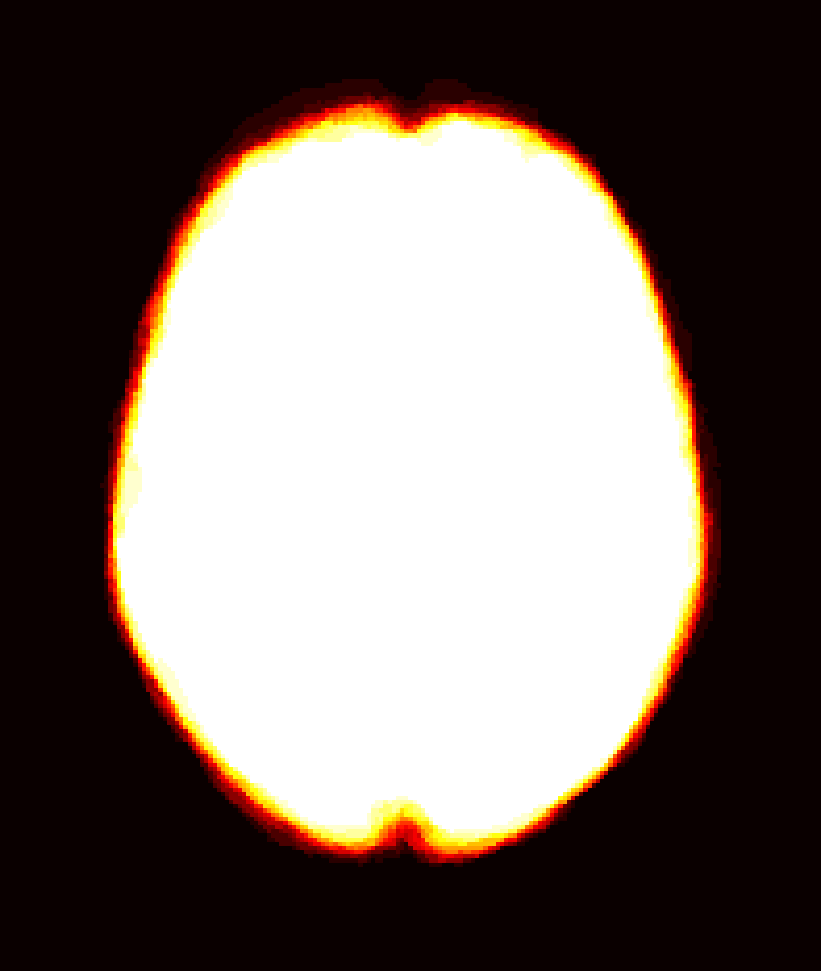

Figure 8: Example BRATS image with its decomposition result in atlas space. (a) Input image after pre-processing; (b) quasi-normal image L+M𝐿𝑀L+M; (c) non-brain image S𝑆S; (d) pathology image T𝑇T.

In addition to extracting the brain from pathological datasets, our method also allows for the estimation of a corresponding quasi-normal image in atlas space, although this is not the main goal of this paper. Fig.8 shows an example of the reconstructed quasi-normal image (L𝐿L) for an image of the BRATS dataset, as well as an estimation of the pathology (pathology image T𝑇T and non-brain image S𝑆S). Compared to the original image, the pathology shown in the quasi-normal image has been greatly reduced. Hence this image can be used for the registration with a normal image or a normal atlas. This has been shown to improve registration accuracy for the registration of pathological images [27]. Furthermore, an estimate of the pathology (here a tumor) is also obtained which may be useful for further analysis. Note that in this example image the total variation term captures more than just the tumor. This may be due to inconsistencies in the image appearance between the normal images (obtained from OASIS data) and the test dataset. As our goal is atlas alignment rather than quasi-normal image reconstruction or pathology segmentation, such a decomposition is acceptable, although we could improve this by tuning the parameters or applying regularization steps as in [27].